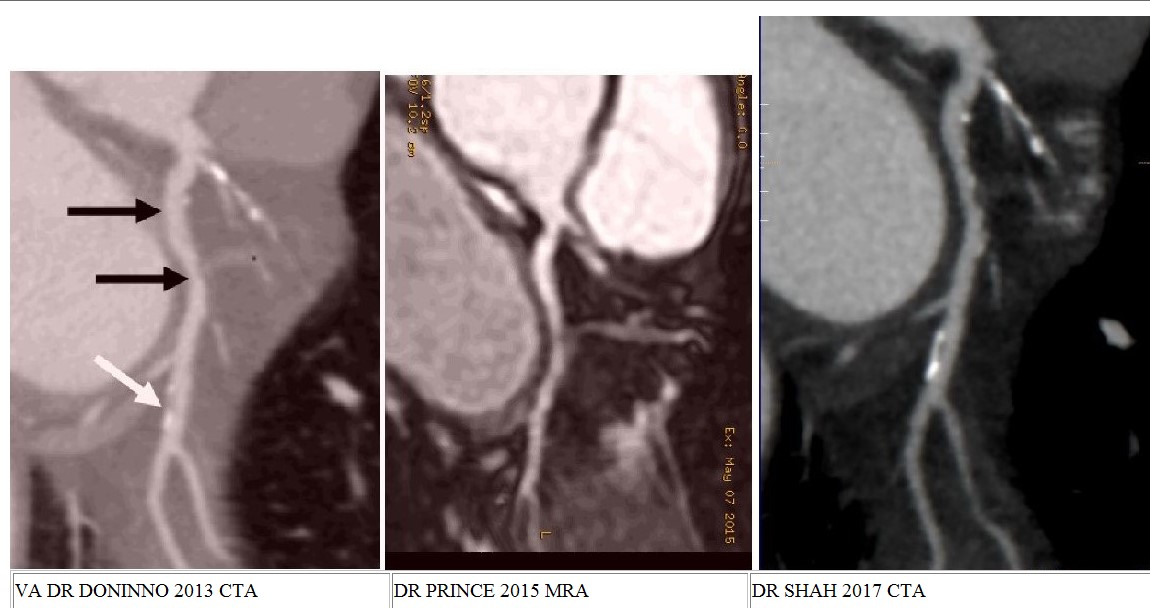

CTA Imaging for heart disease using a 640 Slice CTA 7. From the 3 photos below you can see kinda see the clarity that the 3 different types of imaging I had done and what each machines produces, unfortunately I still see my disease in the 3rd and best picture, so in 4 years the plaque burden evidently remains about the same, so good news. |

2013, CTA of my CFX |

2015 MRA of my CFX artery MRI machine |

2017, 640 CTA slice machine of my CFX artery Dr. Amar Shah location of Northwell CTA |